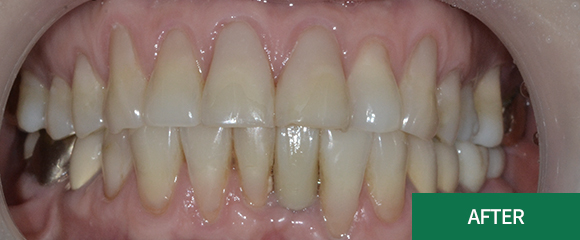

잇몸치료

잇몸치료가 전공 분야인 치주과 원장님께서

꼼꼼하고 꾸준하게 잇몸을 관리해드리고 있습니다.

대학병원에서 주로 시행하는 잇몸 수술까지도 가능한

전문의 원장님과 꾸준한 잇몸관리를 받으시길

바랍니다.